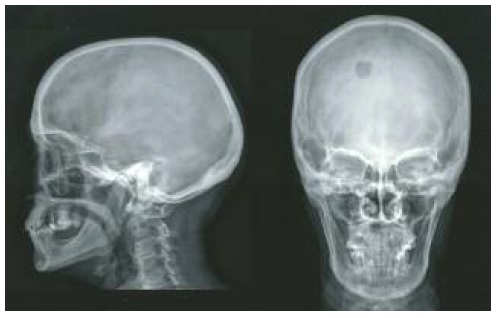

No exame objetivo, à palpação, apresentava uma área mole e dolorosa na calote craniana, com cerca de 1cm de maior diâmetro, localizada na região parieto-occipital direita, com aparente integridade dos tecidos subjacentes e sem lesões cutâneas. No exame neurológico não apresentava qualquer alteração. No entanto, atendendo à preocupação da doente e do médico, realizou uma radiografia do crânio (09.10.2018), onde se observou uma imagem de morfologia arredondada e hipertransparente, localizada na vertente para-mediana direita da região occipital, traduzindo uma alteração de natureza indeterminada (Figura 1). A investigação laboratorial, nomeadamente hemograma completo, parâmetros da inflamação, albumina, β2-microglobulina, metabolismo fosfo-cálcico, função renal e biomarcadores oncológicos, não revelou alterações.

Figura 1 Radiografia do crânio mostrando a lesão de morfologia arredondada e hipertransparente, localizada na vertente para-mediana direita da região occipital.

Os achados radiográficos dos meningiomas intradiploicos são limitados e não são patognomónicos devido à sobreposição das estruturas ósseas. Uma lesão redonda associada a alterações cranianas locais é uma das características radiográficas mais comuns nos MEP da cabeça.7 A radiografia simples do crânio pode detetar anormalidades, geralmente no tipo osteoblástico. A hiperostose, calcificação irregular e marcas vasculares atípicas podem ser observadas em alguns casos.1 O tipo osteolítico pode ser visualizado com uma aparência hipodensa em radiografias simples.

No caso descrito, a doente tinha 58 anos e não apresentava história de trauma significativo ou fratura craniana antiga. Não se verificou a presença de alterações neurológicas atribuídas à lesão; contudo, ficou patente a inespecificidade dos sintomas que pode estar presente numa fase inicial. Apresentava os rastreios oncológicos atualizados, de acordo com a faixa etária e com resultados normais. A investigação laboratorial não revelou alterações. Na radiografia, a lesão apresentou-se como uma imagem de morfologia arredondada e hipertransparente, traduzindo a sua natureza osteolítica. A TC-CE confirmou a lesão lítica na calote craniana, associada a erosões completas da tábua interna e externa do crânio e do espaço diploico. Na RM-CE, a lesão exibia discreto componente epicraniano, pequeno extra-axial intracraniano e aparente base de implantação dural, mas sem dural tail. A doente foi submetida a craniotomia para exérese do tumor e cranioplastia com material sintético. O pós-operatório decorreu sem intercorrências. A doente mantém seguimento em neurocirurgia, onde fará reavaliação imagiológica posterior no sentido de confirmar a ausência de recidiva.